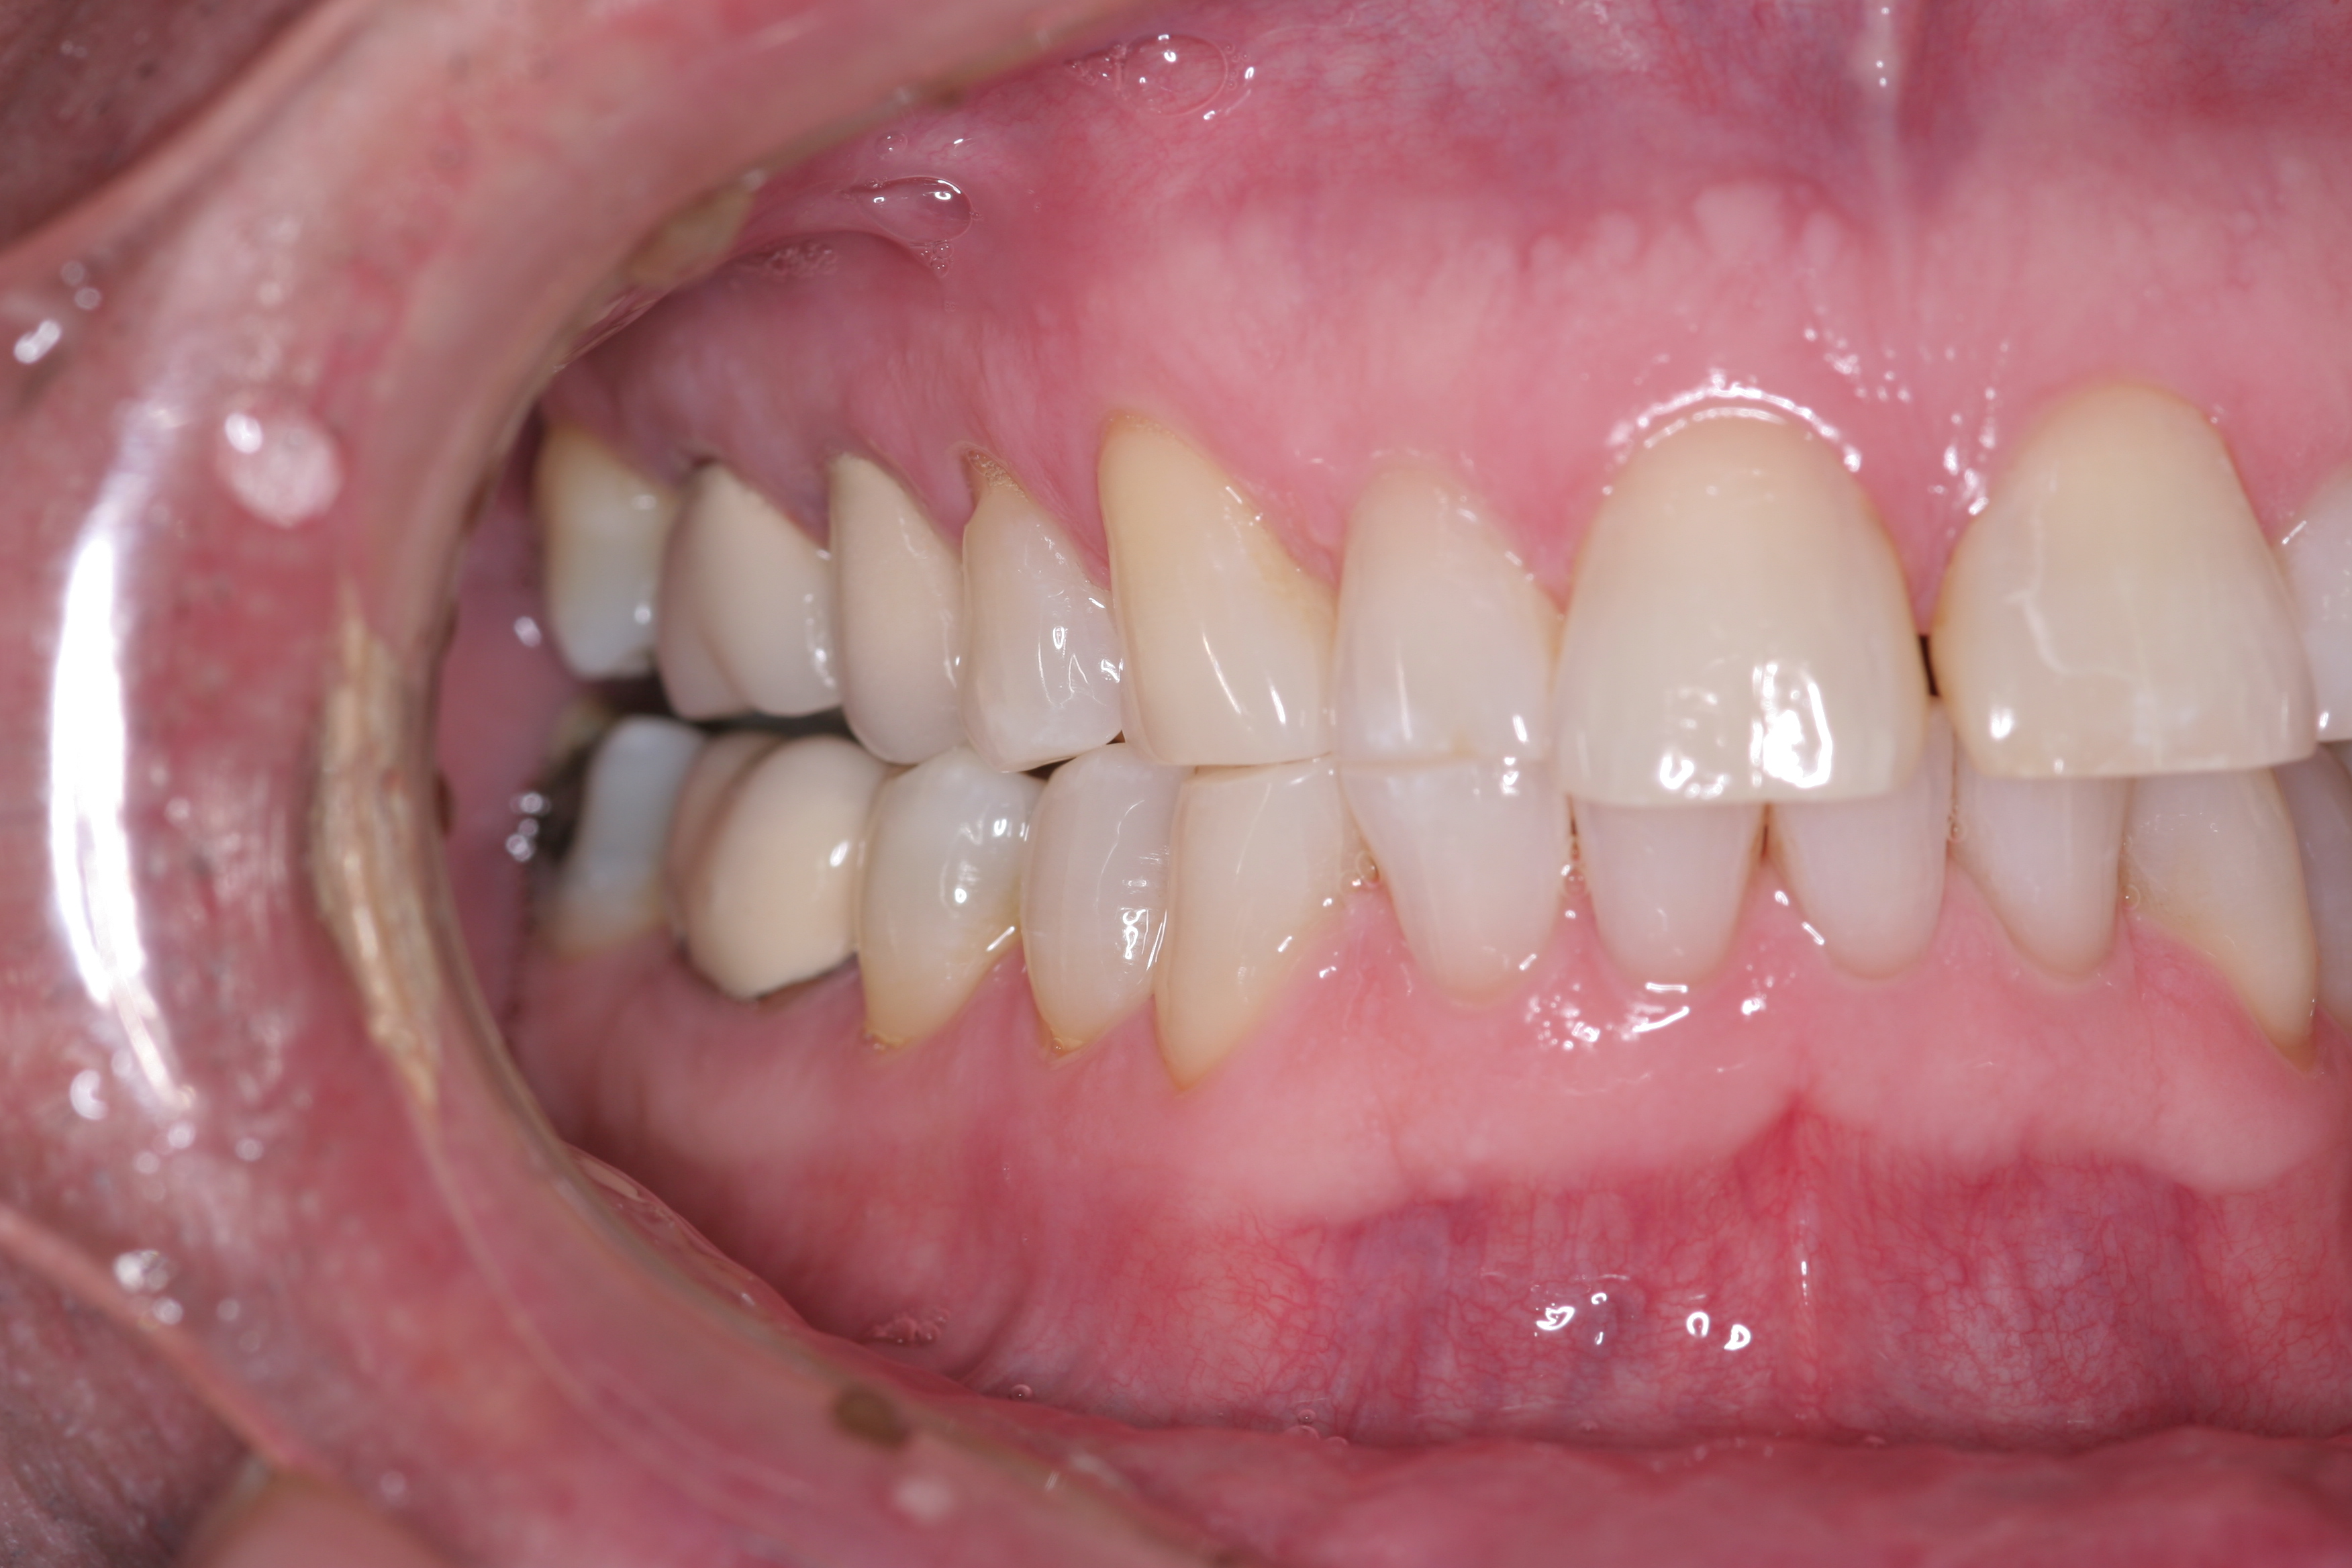

(4.) CR/MIP discrepancies are very common and are major factors leading to excessive tooth-to-tooth abrasion.

Figure 4

True parafunctional bruxism is often rooted in central nervous system–mediated factors and can be influenced by psychosocial and peripheral factors.6 Parafunction may be conscious or unconscious. Either form involves excessive rubbing together of the dentition (Figure 3). CR/MIP discrepancies are very common and are major factors leading to excessive tooth-to-tooth abrasion (Figure 4). CR is the stable axial position the condyle reaches in the most superior and medial aspect of the glenoid fossa. According to Dawson, CR is the only condylar position that allows an interference-free occlusion.1 When the muscles of mastication contract, the condyles will seat into this anatomical position as long as there are no tooth contact interferences preventing the seat. Ideally, when a person closes, the joint will stay seated in CR and all the teeth will come in contact at the same time. Harmony will exist between seated joints and tooth contact.1 If the condyle is seated and the mandible rotates to allow full intercuspation, and posterior tooth inclines contact first, then the mandible slides down and forward around the interferences so that full tooth intercuspation can occur. However, this causes the condyle to be pulled out of CR and braced down the articular eminence by the lateral pterygoid muscle.7 This lack of harmony causes excessive wear as the teeth try to dictate MIP and the muscles work to seat the joint fully into CR. Tooth structure will often lose this “war” between muscles and teeth, resulting in excessive wear or breakage. Symptoms can also be evident in the temporomandibular joints (TMJs) and muscles themselves. This is why a complete examination reviewing all components of the stomatognathic system is critical. Although this topic is beyond the scope of this article, a complete diagnosis cannot be stressed enough.